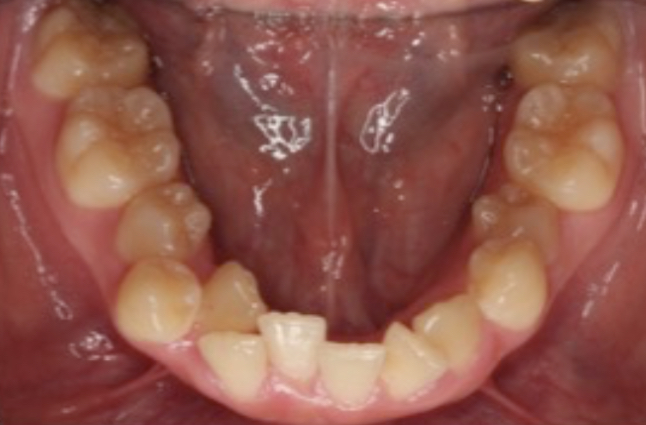

矯正前↓

“歯のガタガタが強くて歯磨きがしにくい”

という方が多くいらっしゃいます。

歯並びがガタガタしていると、

歯ブラシが当たりにくく

汚れが残りやすくなります。